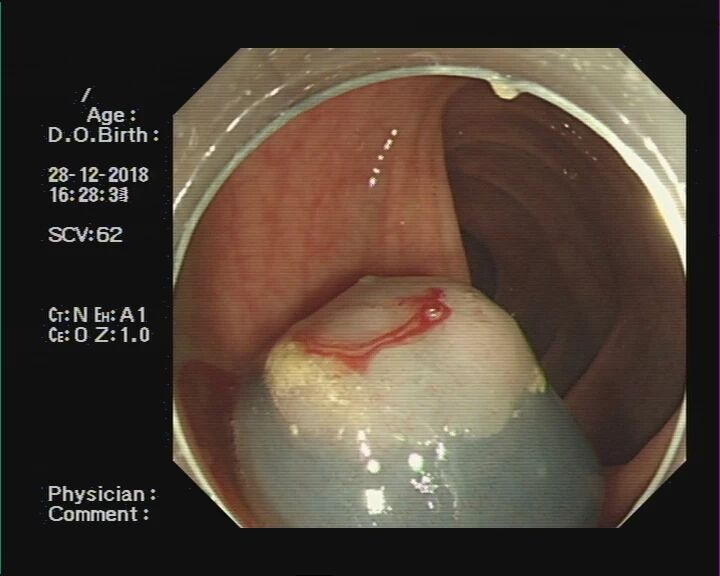

让我们通过肠镜下图片,来了解一下息肉切除的几个步骤:

步骤一:发现息肉,并将其暴露于视野正中。

步骤二:通过肠镜上的孔道插入特殊器械(电圈套器),并在息肉旁伸出钢丝圈。

步骤三:将钢丝圈套住息肉,并于息肉根部收紧钢丝圈。

步骤四:轻轻向肠腔内提起息肉,使钢丝圈尽量远离肠壁黏膜。

步骤五:在钢丝圈上脉冲式通高频电进行电灼烧,直至息肉根部被切断,息肉脱落。

步骤六:为防止创面迟发性出血,可以使用金属夹子夹闭创面。本图为夹子在创面旁打开。

步骤七:金属夹子于创面处夹闭。